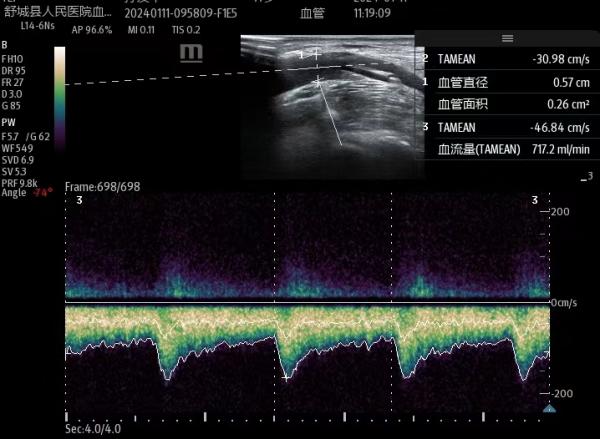

为了让血透患者生命线更通畅,针对疑难血管的穿刺,医护团队采用超声探头充分评估患者的血管方向,深度和血流量,精准定位可视化穿刺,最大限度减轻患者穿刺的痛苦,获得了很多患者的认可和肯定。为患者高品质透析,高质量生存保驾护航,我们一直在路上!